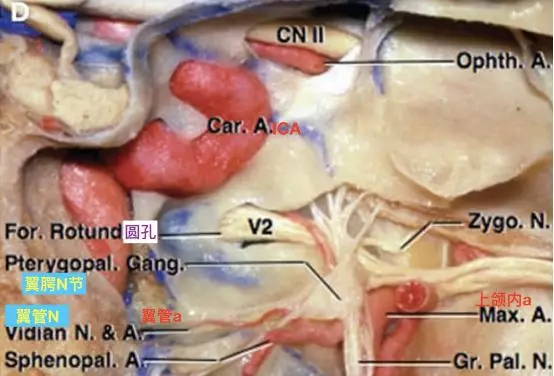

翼管神经和翼管动脉向前走行于蝶窦底下方(Osawa 2009)。可见走行至圆孔,和V2伴行的圆孔动脉。也可见颈内动脉海绵窦段与圆孔的关系也很密切。

要注意在正常情况下,从颈内动脉海绵窦段发出的下外侧干,可能有分支至圆孔处,与上颌内动脉发出的圆孔动脉有吻合。

在颈内动脉起始段狭窄或者闭塞时,上颌内动脉翼腭段可能通过两个分支,对颈内动脉代偿供血。其一通过翼管动脉,经翼管至破裂孔,与颈内动脉岩段发出的翼管动脉吻合代偿供血。其二就是通过圆孔动脉,经圆孔入颅,在圆孔附近与颈内动脉海绵窦段发出的下外侧干形成代偿供血。